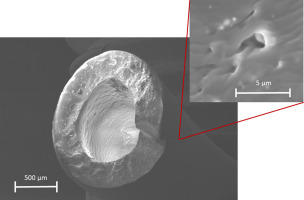

Catheter Rupture Is Due to Material Fatigue of the Implanted Silicone Catheters

American Journal of Roentgenology - September 2017, Volume 209, Number 3 This

Mechanic and surface properties of central-venous port catheters after removal

Journal of the Mechanical Behavior of Biomedical Materials Volume 64, December 2016